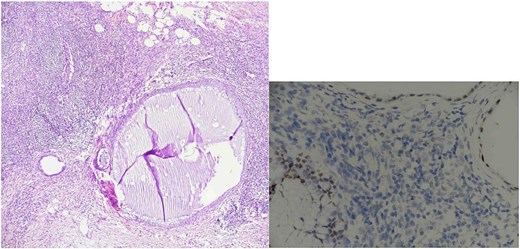

Histopathological analysis showed two reactive lymph nodes measuring 2.0 cm and 3.5 cm. Immunohistochemistry demonstrated positivity for pancytokeratin, estrogen receptor (ER), and CD10, consistent with endometrial tissue. Histopathological images of the lymph nodes are presented in Figs 1 and 2. No signs of malignancy were identified.

Lymph node endometriosis. Lymph node number 1, A: Hematoxylin/eosin stain × 40; B: Estrogen receptor immunostaining × 200.